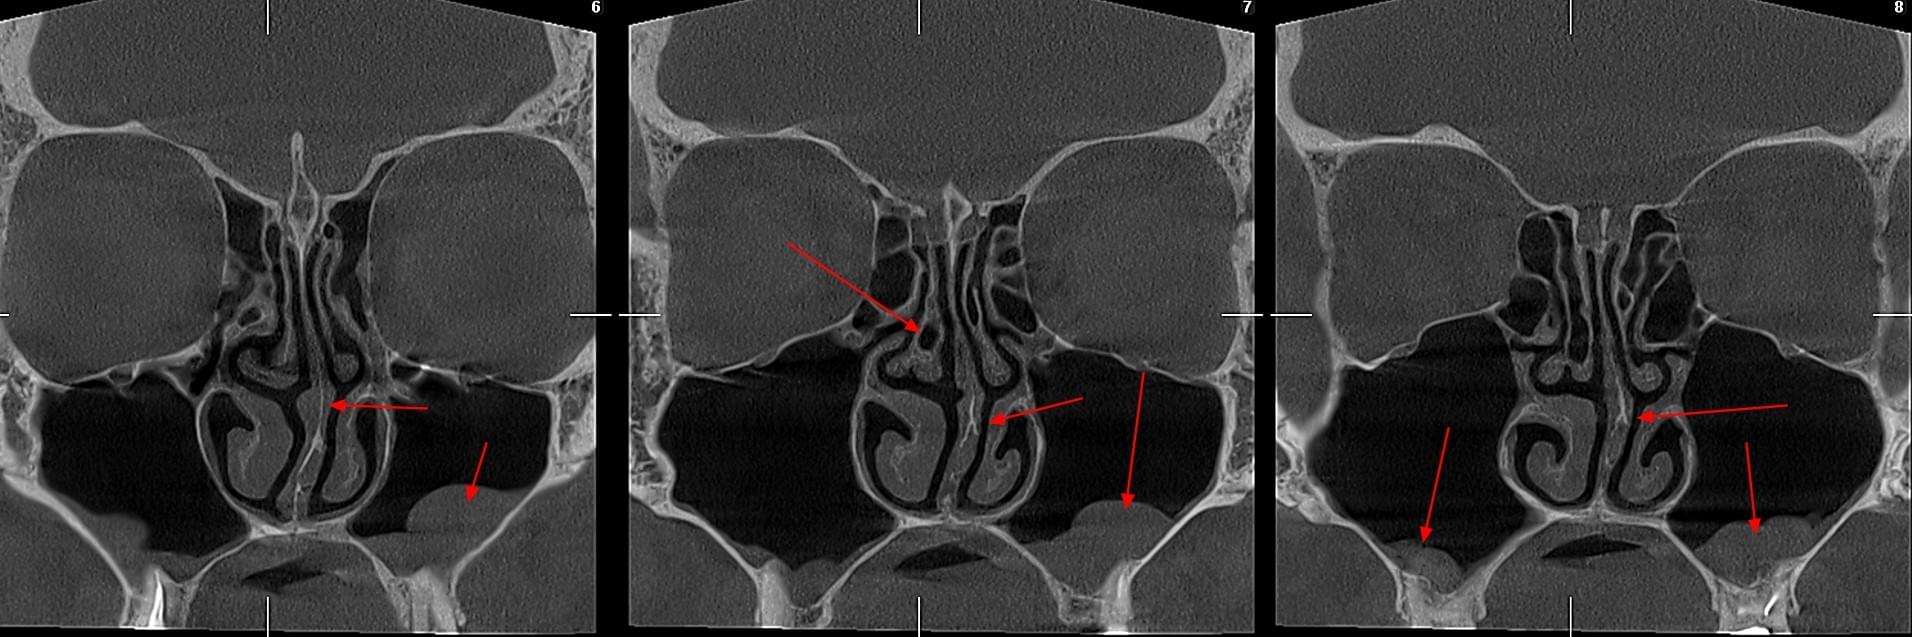

КПКТ (конусно-променева комп’ютерна томографія) — це 3D-знімок високої роздільної здатності. На відміну від звичайного рентгену, КТ показує:

Діагностика гайморових пазух за допомогою КТ

У сучасній медицині КТ придаткових пазух носа (або КТ синусів) — це «золотий стандарт»

діагностики для ЛОР-лікарів та щелепно-лицевих хірургів. Звичайний рентген часто не

показує повну картину, а МРТ не завжди доступний і дорожчий. Комп’ютерна томографія дає

детальну 3D-модель усіх пазух (гайморових, лобних, клиновидних та решітчастого

лабіринту) за 10 секунд і з мінімальною дозою опромінення.